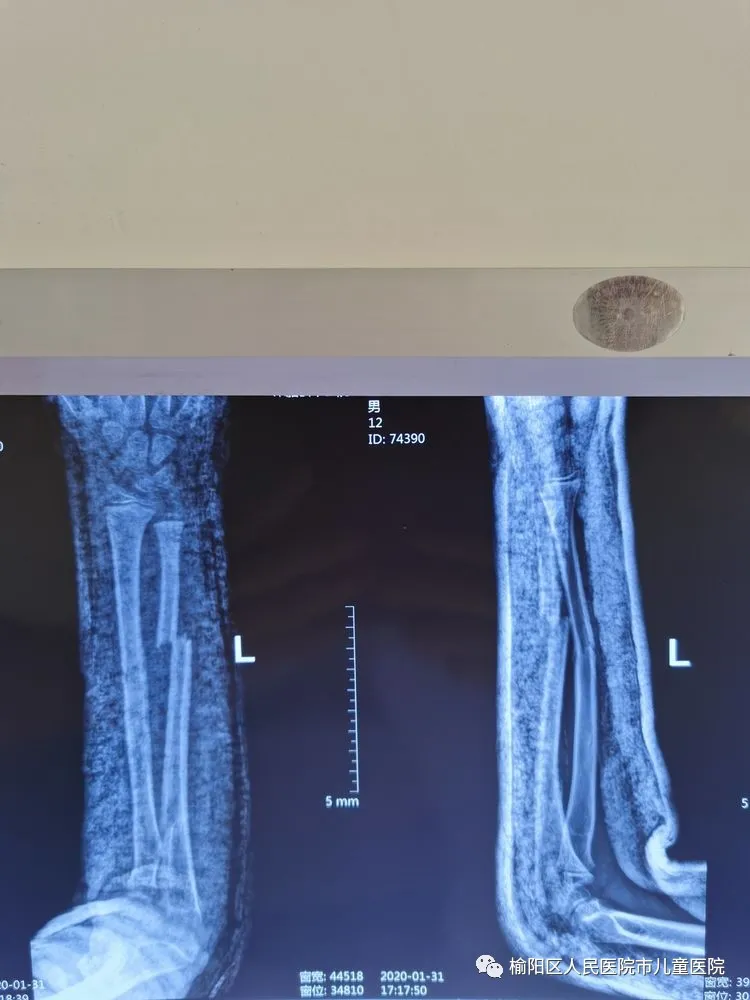

患儿12岁,因外伤致左尺桡骨骨折

复位外固定后家属不满意

在全麻下行弹性髄内针微创闭合治疗